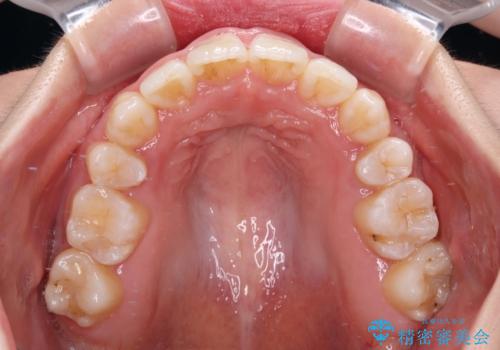

- 上下前歯の八重歯やデコボコと、唇の閉じにくさを気にして来院された患者様です。

口元の突出感を改善するため、上下左右の第一小臼歯4本を抜歯し、ワイヤー装置にて矯正治療を行うこととしました。

デコボコの解消で歯が磨きやすくなり、抜歯矯正により口元の突出感が大幅に改善され、スッキリした口元になりました。